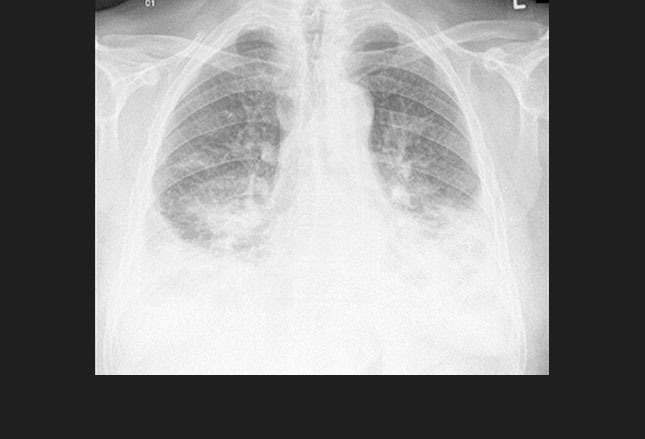

图1. 一位进展性肺结核患者双侧胸腔积液(左侧较右侧严重)。